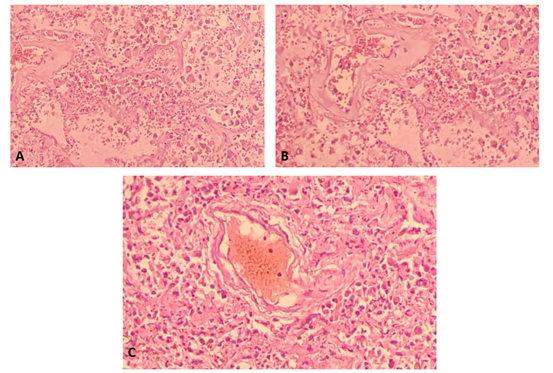

Histological evaluation

Post-mortem autopsy: it was performed to confirm severe SARS-CoV-2 infection, analyzing histological samples of lung tissue obtained by necropsy, determining the exact cause of death and recognizing histological patterns that eventually contribute to guide clinical management (Figure 3).

Figure 3 Histological changes observed in post-mortem autopsy.

A) Section of lung tissue shows pulmonary alveoli filled with acute inflammatory cells, macrophages. Increased fibro connective tissue in some alveolar septa and hyaline membrane formation resulting in respiratory distress.

B) Interstitial fibrosis, rupture of alveoar septa with acute intralaveolar and septal inflammatory response.

C) Vascular thrombosis associated with an inflammatory process and interstitial fibrosis.

The histological images translate what was evidenced in the imaging studies such as: diffuse alveolar damage in the organization phase with fibrosis, which was decisive for making therapeutic decisions, marking the patient's prognosis. In addition, the evidence SARS-CoV-2 testing can be done at autopsy. Autopsy findings such as diffuse alveolar damage and airway inflammation reflect true virus-related pathology. Other findings represent processes that are superimposed or not related to the disease under study. In this case, the patients with COVID-19 presented diffuse alveolar damage with the formation of hyaline membranes, mononuclear cells, and macrophages that infiltrate the air spaces, also with diffuse thickening of the alveolar wall.2

Wichmann et al also found a high incidence of thrombotic events, which suggests that the COVID-19 virus induces severe endotheliitis and abnormal activation of the coagulation cascade. For this reason, further studies are required to explain these findings, and eventually achieve a possible therapeutic intervention in the near future.2,6 Finally, Merad described micro thrombi at different levels in patients with COVID-19: lungs, lower extremities, hands, brain, heart, liver and kidneys, suggesting that coagulation activation and intravascular coagulation are data of an organic lesion in sepsis that is mainly associated with inflammatory cytokines and with the participation of the pathway tissue factor (abbreviated TF; also called CD142 or coagulation factor III) and which undoubtedly contributes to the greater severity of patients.2,7